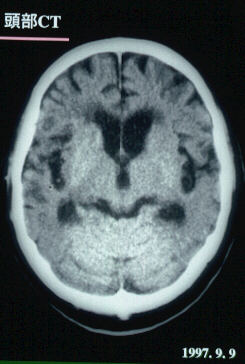

1997.9.9:頭部CTスキャン

脳浮腫は改善。脳出血部位も吸収されている。